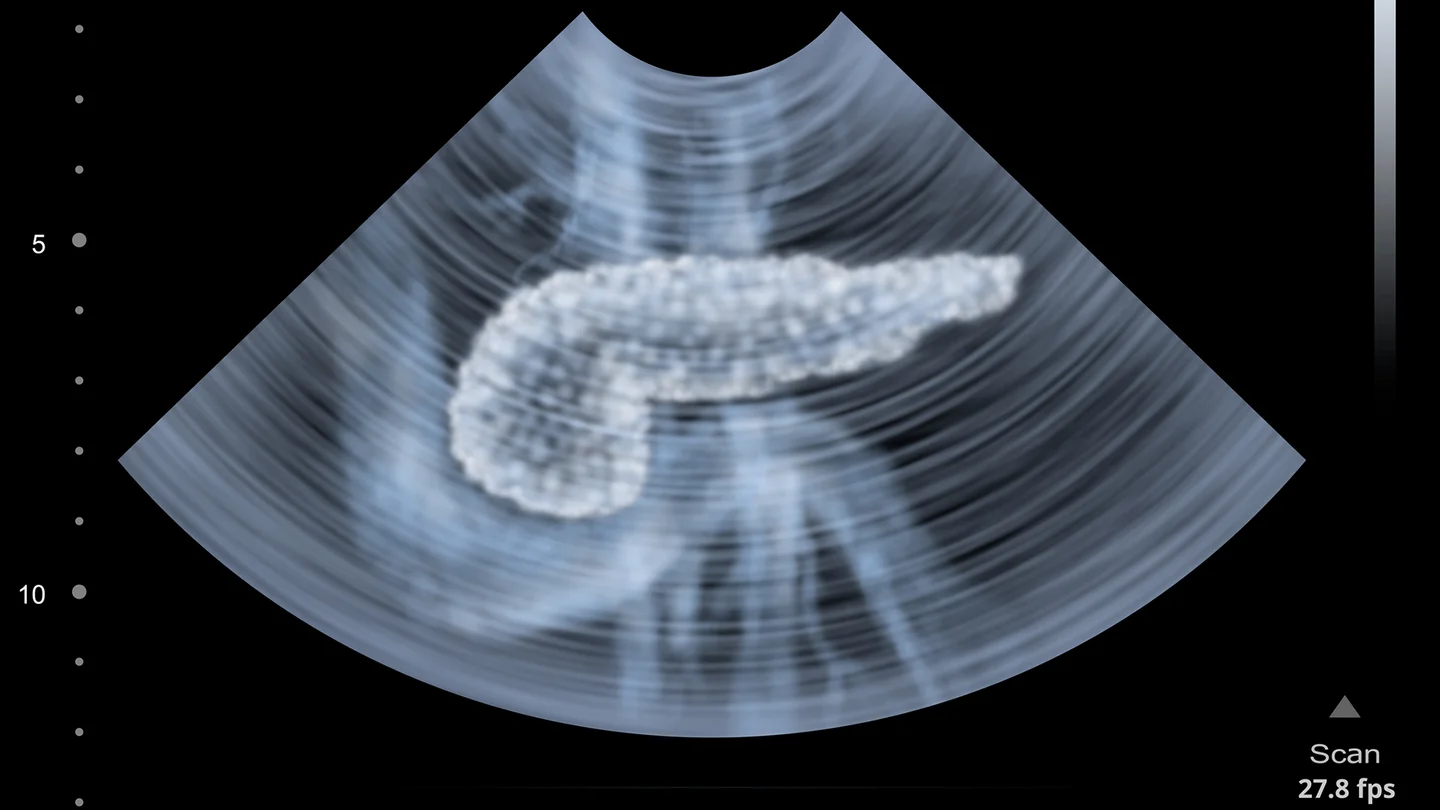

Bauchspeicheldrüsenkrebs: Ein Ultraschallbild, auf dem ein menschlicher Pankreas abgebildet ist. Bauchspeicheldrüsenkrebs: Ein Ultraschallbild, auf dem ein menschlicher Pankreas abgebildet ist.